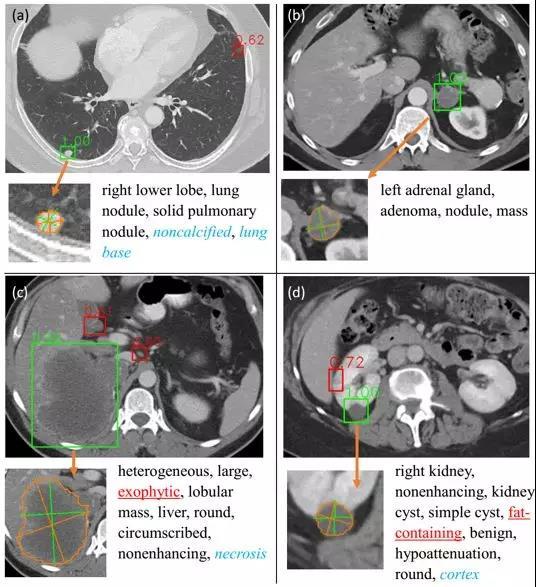

平安科技人工智能中心的研究尝试将检测、描述和分割三个任务结合起来,基于合作伙伴NIH发布的DeepLesion数据集,平安科技人工智能中心开发了通用病灶检测系统、描述系统和分割系统,并通过一个实例分割框架将这三部分有机地结合在一起,同时辅助以3D特征融合策略和决策调整策略来利用病灶描述结果改善病灶检测精度。

该研究在DeepLesion数据集上取得了通用病灶检测的最好精度,超过了之前结果最好的帝国理工大学团队。

图四:通用的病灶检测系统,先看出病灶长在哪里,再进行自动分类测量